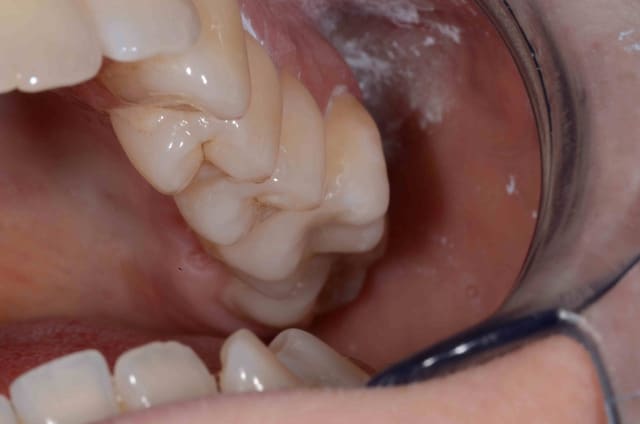

Quelques réalisations en vrac

après avoir bien galéré avec la version 3.85 je mets en ligne un cas de 6 cérams faites à partir des modèles scannés avec cerec.

D'abord les biscuits, modèles d'origine (2005), situation actuelle, puis couronnes glacées.

Blocs VITA Triluxe Forte 12.